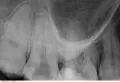

Недавно поставил металлокерамическую коронку на передний зуб верхней челюсти, а сейчас появилась на нёбе шишечка (в виде мозоля). Сделал рентген зуба, показало кисту, как врач сказал приличного размера, что уже поразило костную ткань и достаёт на небо.

При наличии кисты крупного размера кроме удаления зуба стоит рассмотреть возможность резекции верхушки корня.

На передних верхних зубах данная манипуляция имеет положительный прогноз.